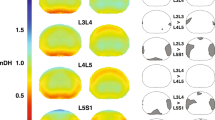

All vertebral motion segments, L2–3, L3–4, L4–5 and L5–S1, rotated similarly during the lifting motion. L4–5 showed the largest anterior-posterior (AP) translation with 2.9 ± 1.5 mm and was significantly larger than L5–S1 (p < 0.05). L5–S1 showed the largest proximal–distal (PD) translation with 2.8 ± 0.9 mm and was significantly larger than all other motion segments (p < 0.05).

The lower lumbar motion segments L4–5 and L5–S1 showed larger AP and PD translations, respectively, than the higher vertebral motion segments during the weight-lifting motion. The data provide insight into the physiological motion characteristics of the lumbar spine and potential mechanical mechanisms of lumbar disease development.